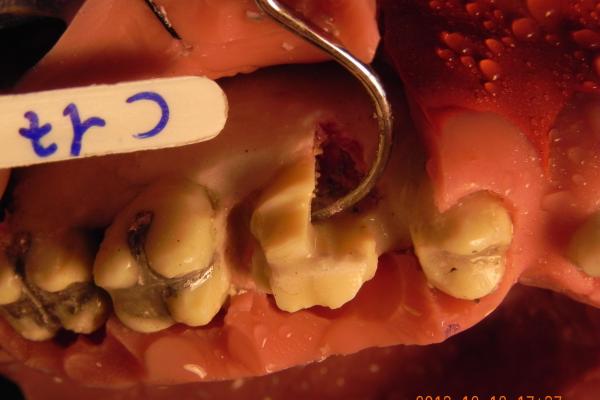

I manichini utilizzati per gli interventi chirurgici sono molto realistici e sono fatti anche con tessuti di animali per cui lavorare su di essi con il bisturi o lo scollaperiostio e le frese per osso è molto simile alla sensazione che si ha lavorando sui tessuti dei pazienti. Alla fine del corso mi hanno consegnato come materiali didattici una serie di membrane per rigenerazione guidata e di materiali osteoconduttori già pronti per usarli sui pazienti. Ho fatto il corso soprattutto per la parte di rigenerazione guidata e per gli allungamento delle corone cliniche ma mi é stato utilissimo anche per gli interventi conservativa di chirurgia parodontale dei quali ho capito la utilità.